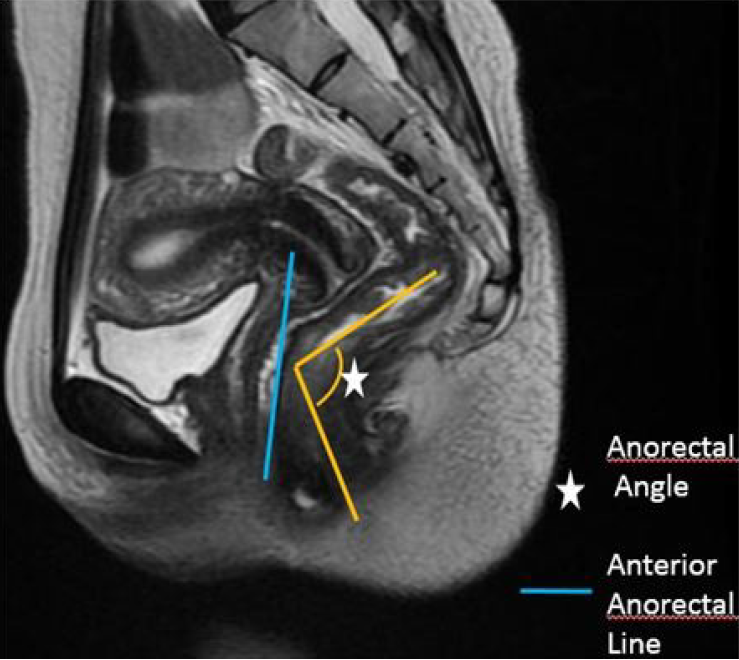

Figure 3 Magnetic resonance images indicating an anorectal angle (typically 90°–130° at rest)[10].

Citation: Megha K, Sushil G K, Dilip L L. Applications and Limitations of Magnetic Resonance Defecography in Evaluation of Pelvic Floor Dysfunction Disorders. Int J Radiol Imaging Technol 2019; 5. Copyright ©The Author(s) 2019. Published by ClinMed International Library (Supplementary material).